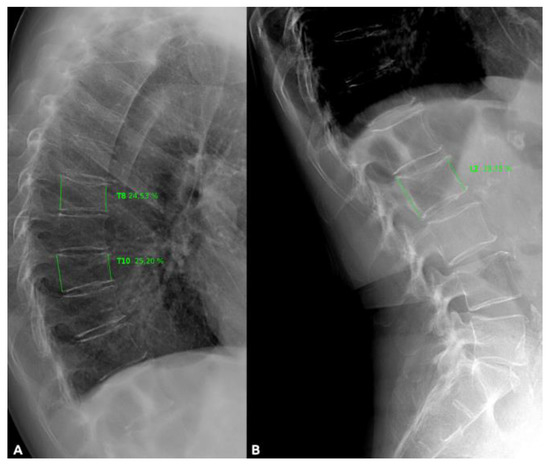

- Genant, H.K.; Wu, C.Y.; van Kuijk, C.; Nevitt, M.C. Vertebral fracture assessment using a semiquantitative technique. J. Bone Miner. Res. 1993, 8, 1137–1148. [Google Scholar] [CrossRef] [PubMed]

| Vertebrae | Vertebral Fractures (n,%) |

|---|---|

| T4 | 0 (0.0%) |

| T5 | 2 (1.0%) |

| T6 | 3 (1.5%) |

| T7 | 7 (3.5%) |

| T8 | 8 (4.0%) |

| T9 | 9 (4.5%) |

| T10 | 11 (5.5%) |

| T11 | 34 (17.0%) |

| T12 | 47 (23.0%) |

| L1 | 45 (22.0%) |

| L2 | 17 (8.0%) |

| L3 | 9 (4.0%) |

| L4 | 5 (2.0%) |

| L5 | 9 (4.0%) |

| Total vertebral fractures | T: 121 L: 85 (n = 206, 100%) |